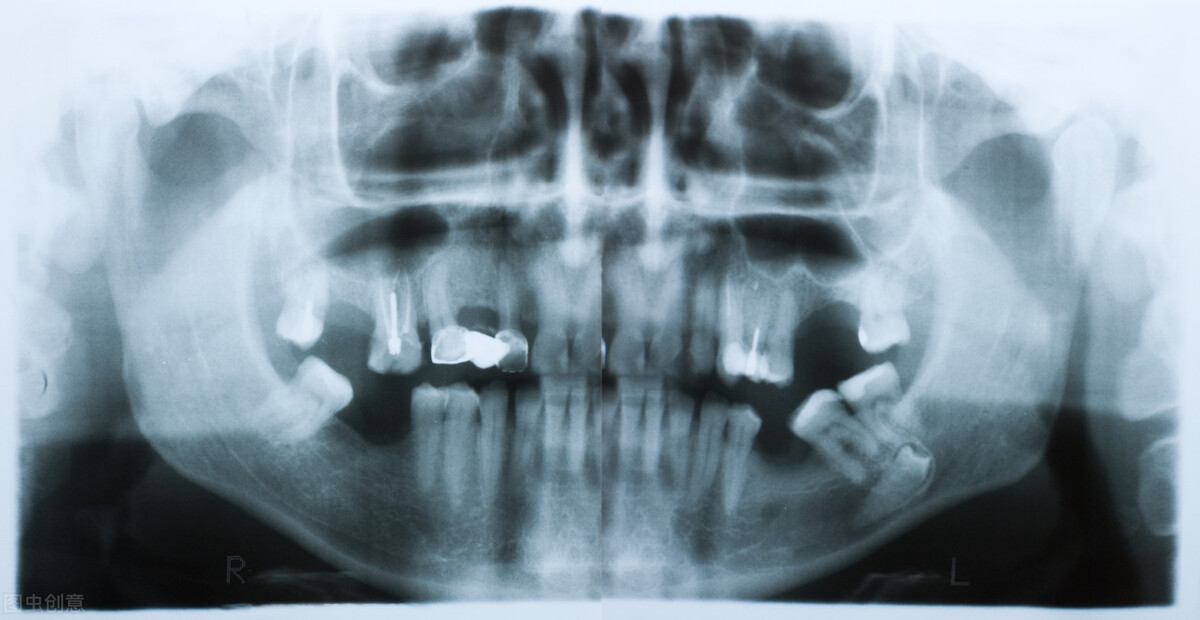

目前在牙科治疗种拍牙片一边分为3类,分别是小牙片、曲面断层片和CBCT三维片。无论是哪一种牙片,目的都是为了能够让医生能够更加清楚地了解患者的牙齿情况,便于做出精准的治疗,提高诊疗成功率以及诊疗过程的舒适度。